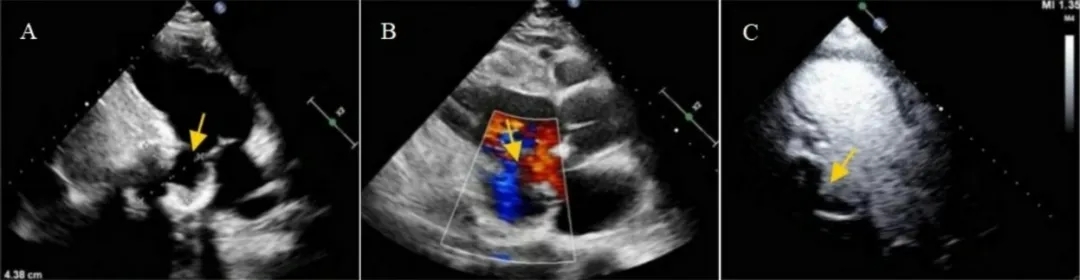

经胸超声心动图(TTE)显示一巨大的周边钙化囊腔,通过一狭窄颈部与左心室相通(图2A和B),同时伴有显著左心室扩大和射血分数降低。对比增强超声心动图确认存在一巨大腔室,边界钙化清晰,基底部下后壁段可见连续性中断(图2C)。

图2:影像学发现长轴切面显示假性动脉瘤(箭头)。(A)以及假性动脉瘤内的双向血流(箭头)。(B)腔内可见造影剂流动(箭头),伴有大范围充盈缺损,提示大量血栓形成(C)。